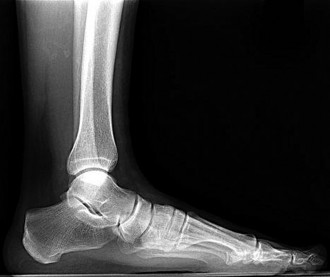

Question 20:

A 58-year-old male with long-standing, poorly controlled diabetes presents with a unilaterally swollen, warm, and erythematous foot without ulceration. Radiographs reveal osseous fragmentation, debris, and joint subluxation in the midfoot, but no significant sclerosis or osteophyte formation. According to the Eichenholtz classification of Charcot neuroarthropathy, what stage does this represent?

Correct Answer: Stage 1 (Development/Fragmentation)

Explanation:

The Eichenholtz classification describes the radiographic progression of Charcot neuroarthropathy. Stage 0 is clinically swollen and warm with normal radiographs. Stage 1 (Development/Fragmentation) features bony debris, fragmentation, joint subluxation/dislocation, and loss of joint space. Stage 2 (Coalescence) is marked by absorption of fine debris, early fusion of fragments, and sclerosis. Stage 3 (Reconstruction) shows consolidation of fractures, remodeling, and mature osteophyte formation.